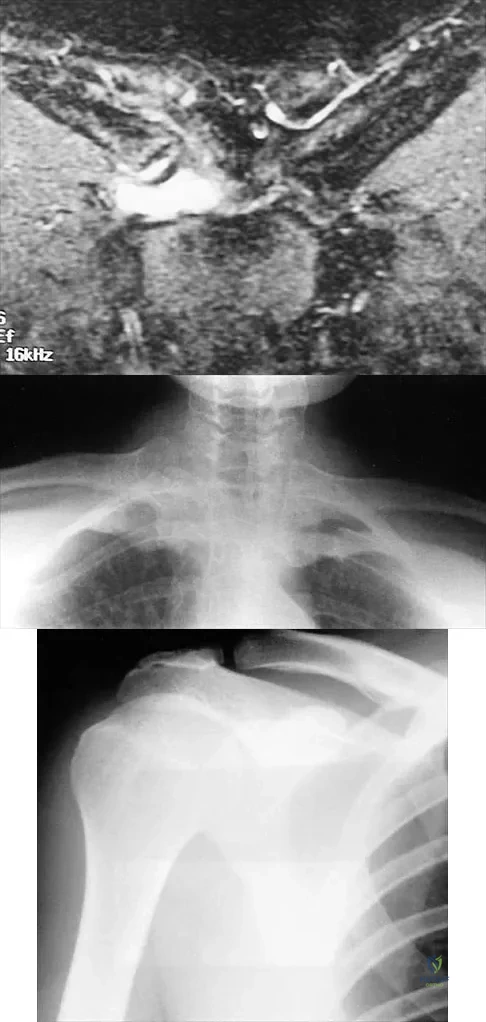

A 43-year-old former professional hockey player reports severe pain in his chest after being checked from the side in a pick-up hockey game. An MRI scan and plain radiographs are shown in Figures 25a through 25c. What is the most likely diagnosis?

Explanation